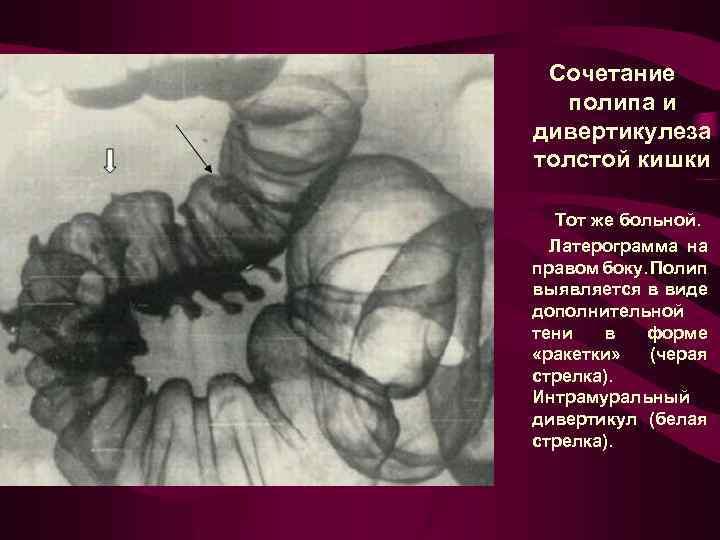

Сочетание полипа и дивертикулеза толстой кишки Рентгенограмма сигмовидной и нисходящей кишки в условиях одномоментного двойного контрастирования в положении больного лежа на спине. Полип на ножке в прямой проекции дает симптом «мишени» (черная стрелка). Ограниченный дивертикулез сигмовидной кишки, множественные полные дивертикулы (белые стрелки).

Сочетание полипа и дивертикулеза толстой кишки Тот же больной. Латерограмма на правом боку. Полип выявляется в виде дополнительной тени в форме «ракетки» (черая стрелка). Интрамуральный дивертикул (белая стрелка).